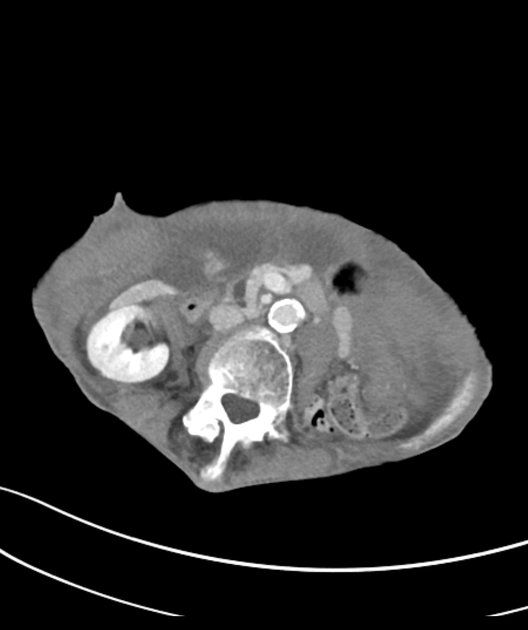

• Xoắn túi mật (Gallbladder volvulus)

• Khí trong đường mật (Pneumobilia)